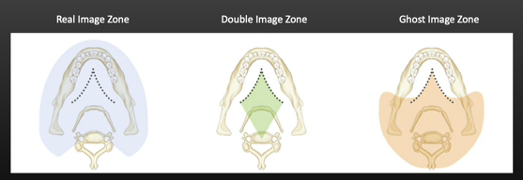

Depending on the locations, 3 different types of objects can appear, what are they?

Real, ghost & double

What is a real image on an OPG?

- Object is between centre of rotation and receptor

- Sharper if closer to focal trough

What is a ghost image on an OPG?

- Object between x-ray source and centre of rotation

- Usually outside of focal trough: appears blurred and magnified

- Appears on opposite side of image (L↔R) and higher on the image (due to upward beam) than their anatomical location

- Mandibular ramus, hyoid bone, cervical spine, earrings, etc.

What is a double image on an OPG?

- Object is posterior to centre of rotation (the red diamond area) and intercepted by beam twice

- Structures in the centre eg. Hyoid bone, epiglottis, cervical spine, palate

- Double images are mirror images, appearing on the same location but opposite sides

Objects that lie posterior to the centre of the xray beam go through the centre of the beam twice and form a double image or mirror image appearing on the same location but on both right and left sides